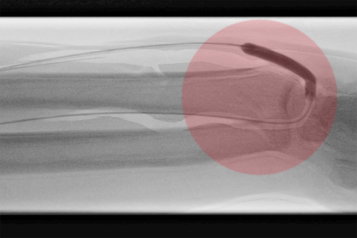

Für interventionelle Behandlungsmethoden ist ein Zugang ins Gefäßsystem notwendig. Dieser wird am häufigsten in der Oberschenkelarterie/-vene im Bereich der Leiste oder der Armarterie/-vene im Ellenbogen- oder Handgelenksbereich angelegt.

Dazu erfolgt nach gründlicher Desinfektion und lokaler Schmerzstillung die Nadelpunktion des Gefäßes mit anschließender Einführung einer Gefäßschleuse (Gefäßventil), die dem Behandler ermöglicht, unterschiedliche Kathetersysteme zur Behandlung ohne Blutungs- und Verletzungsgefahr schmerzarm in die zu behandelnde Gefäßregion einzuführen.